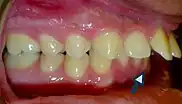

- Patients with increased overjet or lip incompetence are also at a higher risk of suffering traumatic injuries in the upper incisors (Schatz et al., 2020).

Overjet